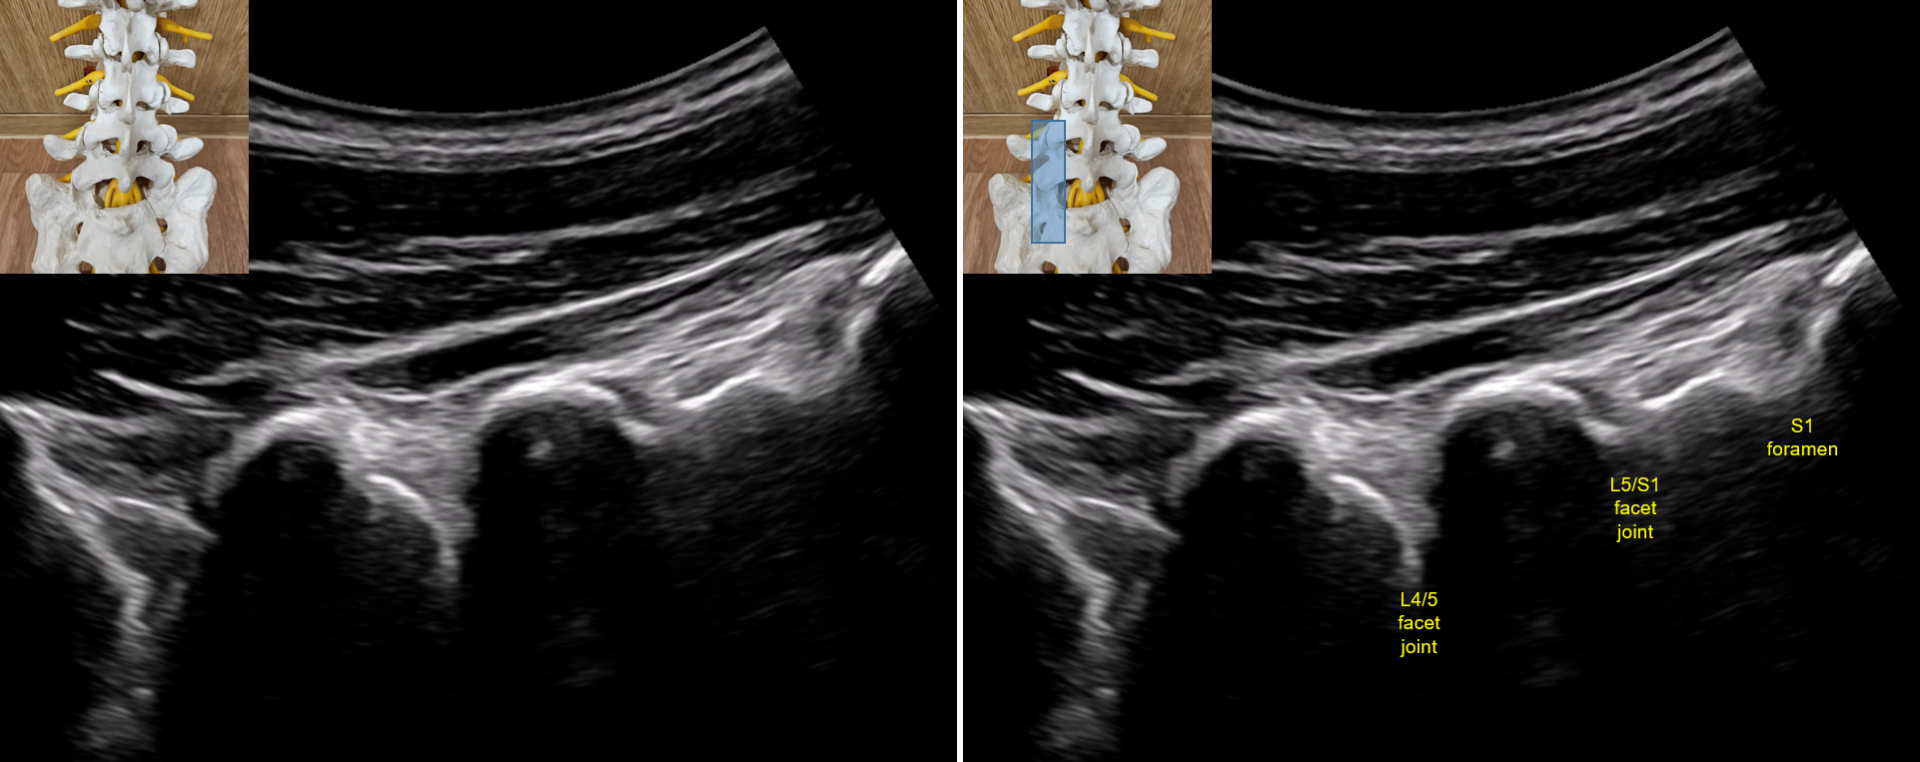

The lecture begins with a structured review of normal lumbar ultrasound anatomy, including the spinous processes, laminae, facet joints, transverse processes, interlaminar spaces, and foraminal regions. Emphasis is placed on recognizing these structures in routine longitudinal and transverse scans, as accurate identification of normal anatomy forms the foundation for all ultrasound-guided interventions.

Building on these fundamentals, the lecture introduces target-specific approaches for pharmacopuncture of the L4, L5, and S1 nerve roots. Learners are guided through the process of transitioning from longitudinal to transverse views, identifying facet-level landmarks, and adjusting probe position to secure an optimal field of view.